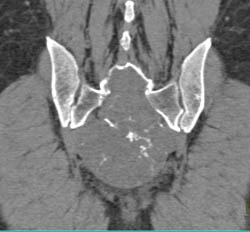

Chordoma